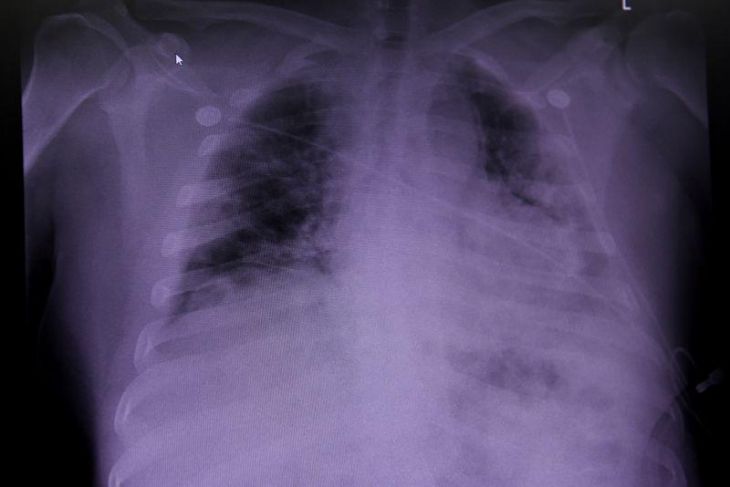

Foto: Reuters

Científicos de Universidad Politécnica de Madrid (UPM) y de la Universidad de Concepción (UdeC), de Chile, desarrollan un modelo de inteligencia artificial capaz de detectar un caso de neumonía de forma inmediata con solo analizar la radiografía de un tórax.

Los especialistas crearon un algoritmo de inteligencia artificial alimentado con diversos biomarcadores que los médicos detectan para diagnosticar la enfermedad tras analizar los resultados de las pruebas de rayos X de los pacientes.

Los resultados de las primeras pruebas de este algoritmo han demostrado una eficacia de 99 por ciento para detectar a pacientes con neumonía.

“Se han definido atributos fundamentalmente relacionados con la textura que presenta la región de los pulmones incluidos en estas imágenes. Estos atributos constituyen los biomarcadores a partir de los cuales generamos los modelos para detectar la neumonía”, continúa explicando Consuelo Gonzalo de la UPM.